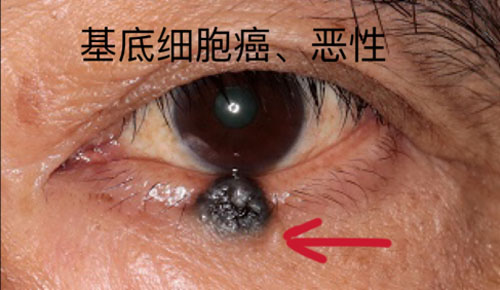

眼肿瘤包括眼睑、结膜、眼内、泪器、眼眶肿瘤。眼睑恶性肿瘤常见基底细胞癌,睑板腺癌、鳞状细胞癌和黑色素瘤,良性肿瘤常见于色素痣和血管瘤;眼眶肿瘤包括淋巴瘤、腺样囊性癌、海绵状血管瘤、神经鞘瘤、神经纤维瘤等;眼内肿瘤以恶性多见,主要见于视网膜母细胞瘤、脉络膜黑色素瘤、脉络膜转移癌等。

对于眼睑的肿瘤,会充分考虑到颜面部的美容需要,在确保清除病变的同时,完成整形修复。眼睑肿瘤表现多种多样,良性病变多生长缓慢,边界清楚。但是如肿块突然增长加速,有破溃、出血,疼痛,色素性肿块有色素播散现象时,您必须引起高度重视。绝大部分恶性肿瘤都发生在中老年人,而年轻人的眼睑肿块多是炎症变化。

如果您到医院就诊,医生借助放大仪器可以更清楚地观察病变。部分恶性病变的早期难以完全凭临床经验确诊,医生会建议您手术活检,通过病理来确诊。若是恶性,手术切除治疗是首选疗法,切除的范围取决于肿块的大小、位置、深度。皮片移植或皮瓣转移、游离带结膜脸板移植、口唇或聘粘膜移植等方法可以修复肿瘤切除后遗留的巨大缺损。眼睑“寸土寸金”,即使肿块只相差1毫米,手术也会由简变繁,所以早治疗是重中之重。